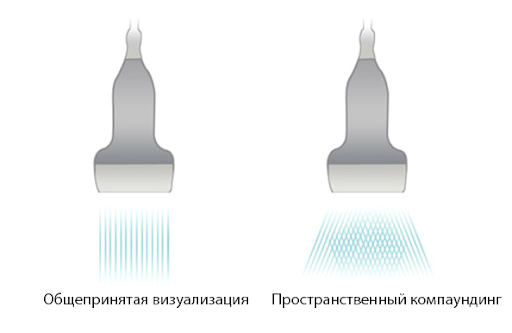

iBeam

Повышение контраста за счет объединения нескольких изображений, полученных под разным углом.